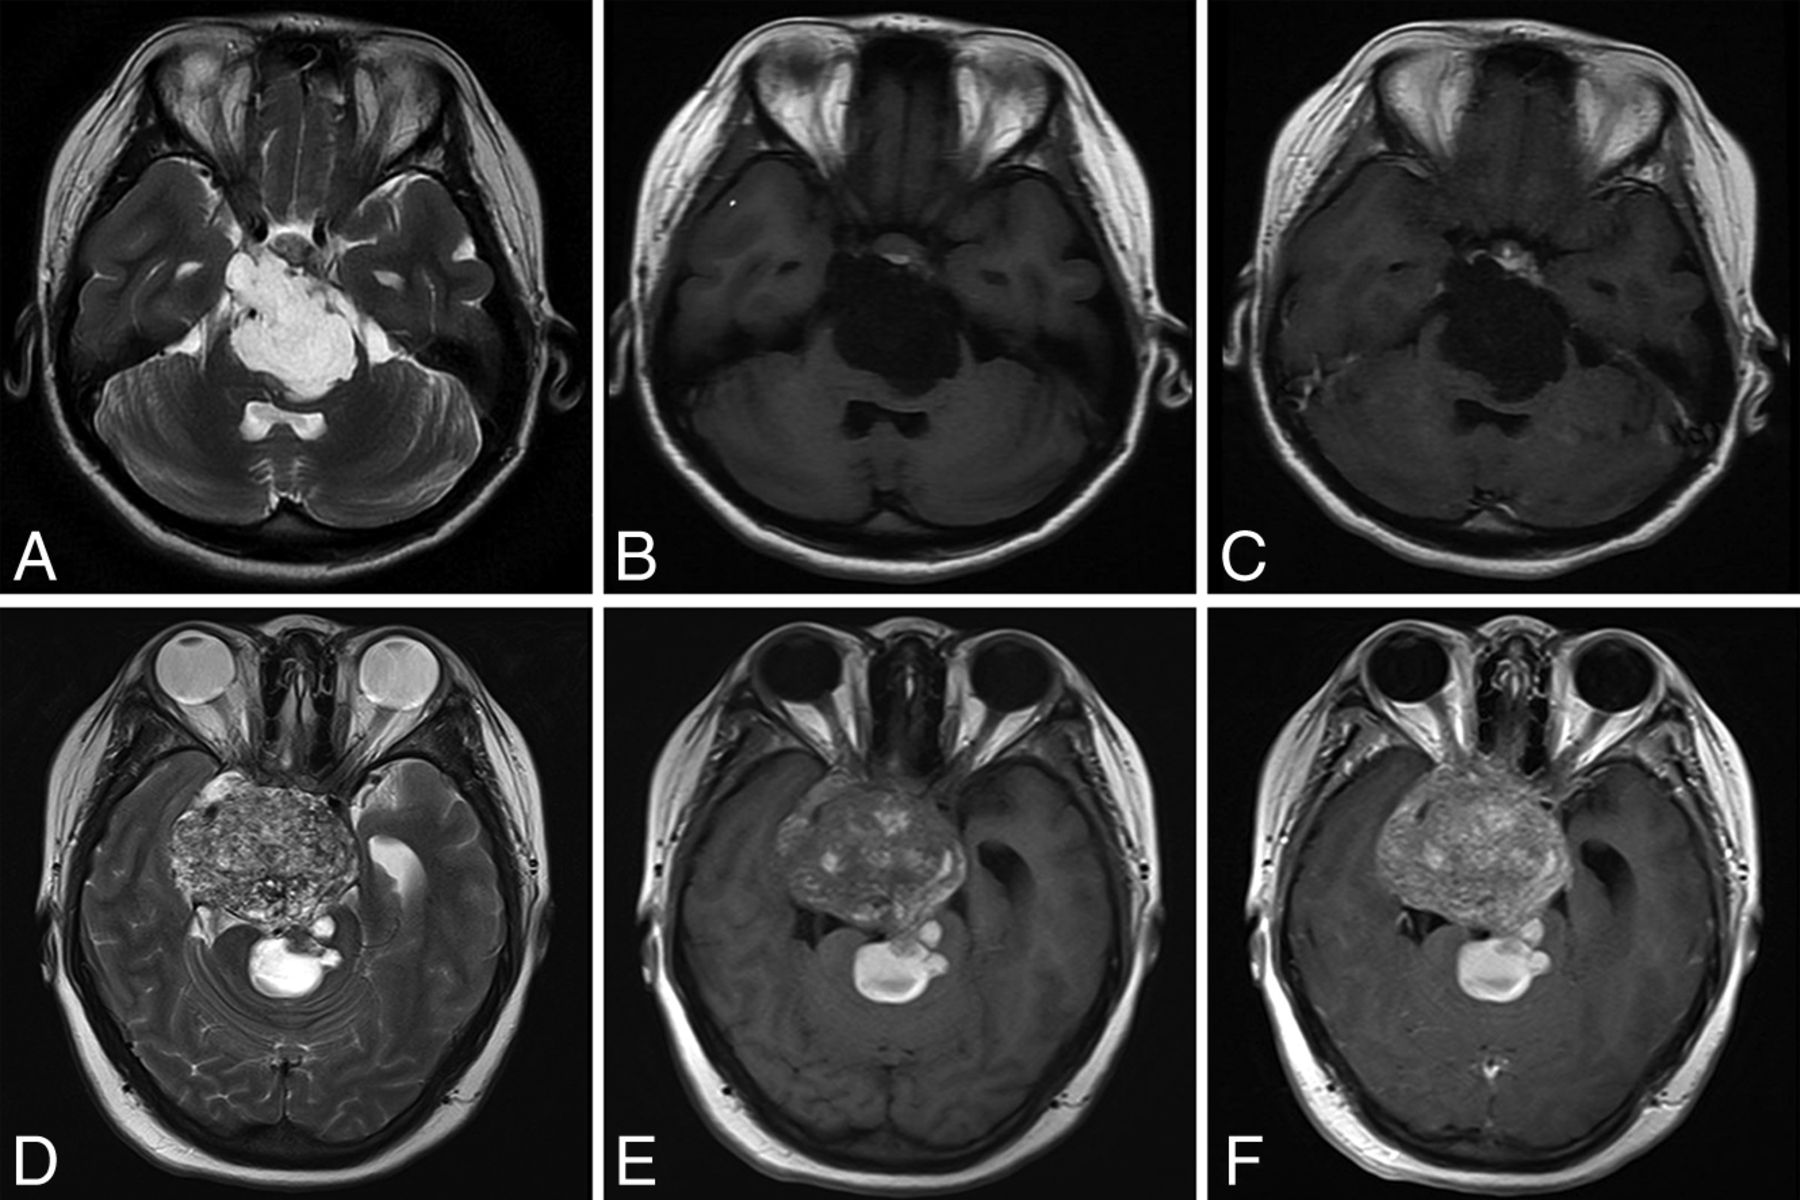

The diagnosis and classification of chordoma primarily depend on histopathologic evaluation and preoperative imaging data. Chordoma has 3 histologic types: conventional, chondroid, and dedifferentiated.15 Conventional chordoma is the most common type, and patients with chondroid chordoma are reported to have the best prognoses.8 Chordoma often shows low density and bone destruction on CT.16 MR imaging is superior in detecting the tumor and delineating its extent.17 Chordomas have a highly heterogeneous appearance on MR imaging, demonstrating hypo- to isointensity on T1 sequences and moderate-to-very-high intensity on T2 sequences. The tumor may exhibit minimal-to-moderate enhancement on enhanced T1 sequences (Fig 1). The clinical significance of this MR imaging heterogeneity has not been discussed in the literature, to our knowledge.

MR imaging of 2 patients with SBC. Patient 1 (A–C), 21-years of age. Pathologic findings were conventional chordoma. The patient underwent subtotal tumor resection with no progression at 48 months. A, Axial T2-weighted MR imaging. Tumor demonstrates homogeneous high signal intensity. B, Axial T1 FLAIR-weighted MR imaging. Tumor has relatively homogeneous hypointense signal compared with the pons. C, Enhanced T1 FLAIR MR imaging shows no enhancement of the lesion. Patient 2 (D–F), 25 years of age. Pathologic findings revealed conventional chordoma with necrosis and nuclear division. This patient underwent subtotal tumor resection with tumor progression at 8 months. D, Axial T2-weighted MR imaging demonstrates tumor heterogeneity. The signal intensity is relatively lower than that in patient 1. E, Axial T1 FLAIR MR imaging. The tumor is heterogeneous and hyperintense compared with the pons. F, Enhanced T1 FLAIR MR imaging. Tumor exhibits moderate enhancement.